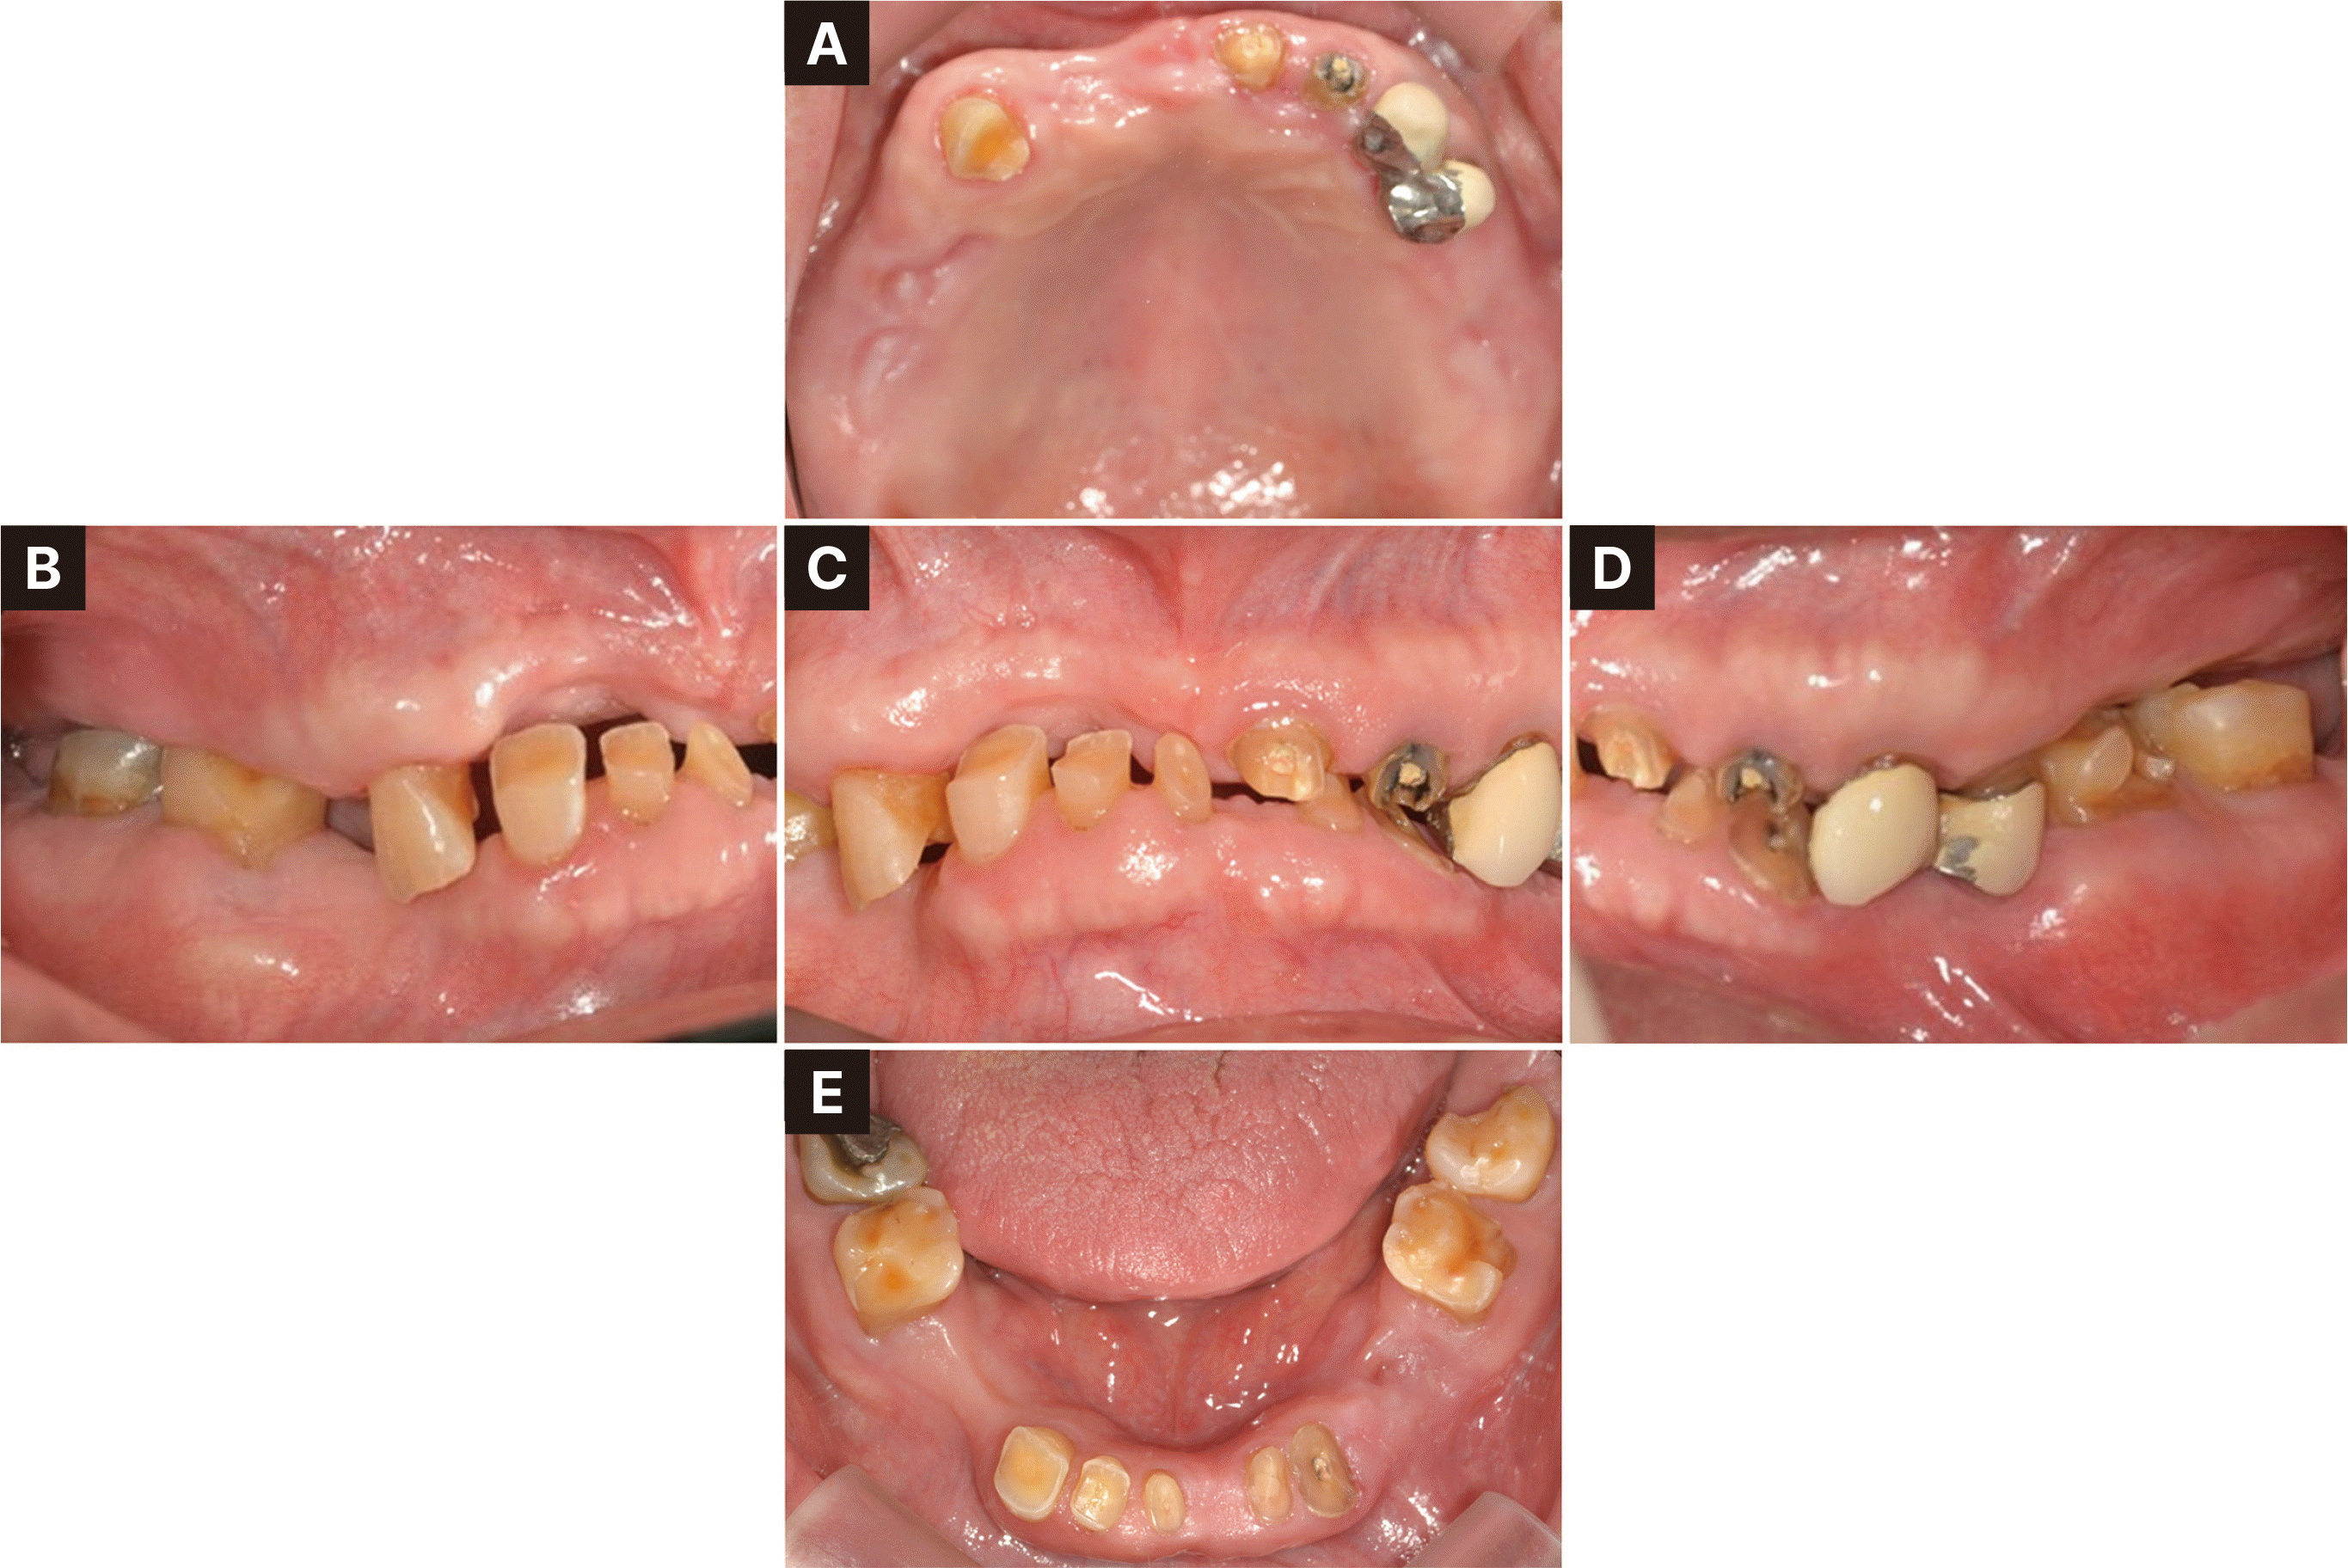

Fig. 3

Pre-operative intraoral photographs. (A) Maxillary occlusal view, (B) Right lateral view, (C) Frontal view, (D) Left lateral view, (E) Mandibular occlusal view.

82세 남자로 다수 치아의 상실을 주소로 내원하였다. 의과력으로 고혈압, 당뇨 및 협심증 병력을 가지고 있었고, 특이할 만한 치과적 병력은 없었다. 파노라마 방사선사진 검사에서 다수의 치아 상실과 전반적인 치조골 소실을 보이나, 잔존한 치아 중 상악 양측 견치와 하악 대구치의 골지지는 양호하였으며, 대구치와 전치들의 치관파절이 있었다(Fig. 1). 좌측 턱관절에서 2016년에서 2020년까지 골변화가 의심되는 소견을 보였다. 그러나 턱관절의 통증과 불편감을 보이지 않았고 임상적으로 안정적인 턱관절 움직임을 나타내어, 적응된 턱관절 관계로 판단하여 보철치료 진행을 결정하였다. 구외 안모평가 시 발달된 저작근과 하악이 전돌된 안모를 가지고 있었다(Fig. 2). 구내 검사 시 습관성 폐구위에서 교합되는 치아가 없었으며 이에 따라, 잔존 치아들이 치조제 점막에 대합되어 뚜렷한 압흔이 관찰되었다(Fig. 3).